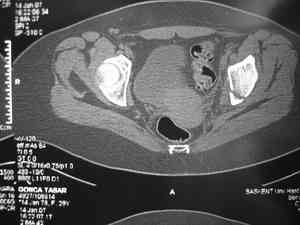

Dear group, 30 years age female MVA front seat, head trauma + post column left acetabular fracture, 2.5 weeks skeletal traction. She is now conscious but still confused without any surgical treatment for brain edema.

Latest X rays and CAT is attached. Fracture within first 1.5 cm from the weight bearing dome, although AP and Obtrator oblique good, iliac oblique view reveals some displacement. I'm not sure that nonsurgical treatment will be OK Hüseyin Demirors Baskent University Dept of Orthopedics and Travmatology Ankara TURKEY